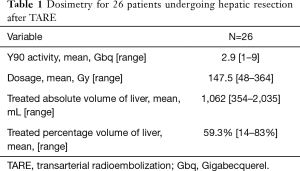

TARE was performed using a previously published methodology (41,42). All patients underwent planning angiography to evaluate the hepatic arterial anatomy. Treatment volumes were calculated using pre-TARE cross sectional imaging for patients treated prior to 2016 and using intra-procedural cone beam CT thereafter. Technetium labeled macroaggregated albumin was administered as a surrogate for radioembolization microspheres. Dosimetry was calculated using the Medical Internal Radiation Dose (MIRD) or Body Surface Area (BSA) methodology for glass (TheraSphere™, Boston Scientific, Marlborough, MA) and resin (SIR-Spheres®, Sirtex, Woburn, MA, USA) microspheres, respectively. All patients received TARE to the planned hepatic future resection site (FRS) with or without an additional selective dose to the tumor(s). The target doses are summarized in Table 1. TARE was used after PVE to salvage an inadequate volumetric response. In some instances, PVE was utilized after TARE per the surgeon’s preference.

TARE dosimetry and target volumes are given in Table 1. The mean treated liver volume was 1,062 mL (354–2,035 mL) and mean treated liver percent was 59.3% (14–83%). The mean Y90 dose was 147.5 Gy (48–364 Gy).